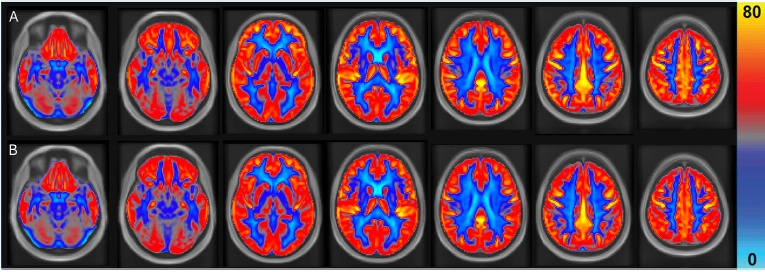

네덜란드 마스트리히트대 의료센터 영양·대사·전달 연구팀이 60세 이상 노인 31명(평균 연령 67세)을 대상으로 16주 동안 매일 땅콩 60g을 섭취하도록 한 결과, 땅콩을 먹은 그룹은 그렇지 않은 그룹보다 뇌 혈류량이 3.6% 증가했다.

특히 회백질(4.5%), 전두엽(6.6%), 측두엽(4.9%), 피질 영역(4.3%) 등 인지 기능과 밀접한 부위에서 유의미한 뇌 혈류량 증가가 확인됐다. 연구진은 “뇌 혈류량 증가는 뇌혈관 기능 향상을 의미한다”라고 설명했다.